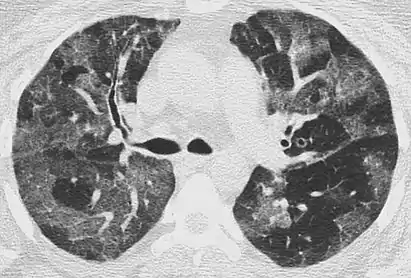

CT image showing centrilobular pattern of GGOs in patient with pulmonary tuberculosis. Note the small, nodular areas of increased attenuation in both lungs.

Centrilobular

Centrilobular GGOs refer to opacities occurring within one or multiple secondary lobules of the lung, which consist of a respiratory bronchiole, small pulmonary artery, and the surrounding tissue.[3] A defining feature of these GGOs is the lack of involvement of the interlobular septum. Potential causes of centrilobular GGOs include pulmonary calcifications from metastatic disease, some types of idiopathic interstitial pneumonias, hypersensitivity pneumonitis, aspiration pneumonitis, cholesterol granulomas, and pulmonary capillary hemangiomastosis.[6]